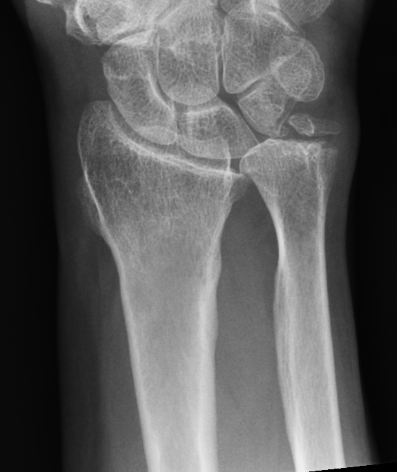

Xray

Bilateral xrays

PA film in neutral

- wrist neutral

- elbow & shoulder at 90°

Malunion

| Radial shortening | Radial inclination | Positive ulna variance |

| Dorsal tilt > 15 degrees | Volar tilt > 10 degrees | Articular step > 3 mm |